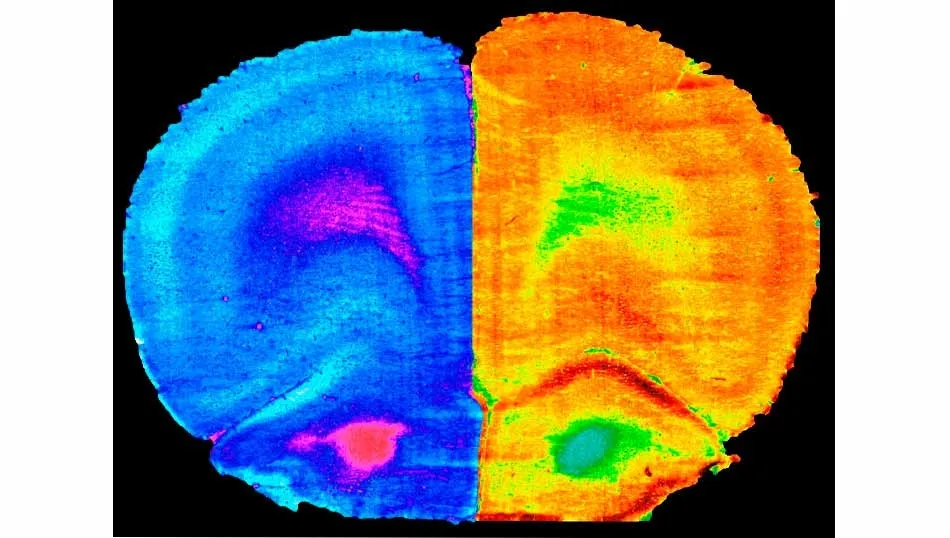

"Hemos descubierto que el deporte y la administración de 'A. muciniphila', no así la de 'L. rhamnosus GG', son capaces de revertir las alteraciones cognitivas asociadas a las dietas altas en grasa y colesterol causantes de numerosas enfermedades hepáticas. Nuestro trabajo ha conseguido una mejora cognitiva en los modelos animales que consumieron una dieta grasa. También hemos observado cambios en la actividad metabólica del cerebro y la composición microbiana intestinal, dos aspectos que habrá que seguir investigando para el diseño de futuras intervenciones en patologías inducidas por la dieta", destaca el investigador del CSIC.

Los resultados obtenidos contribuyen al conocimiento del funcionamiento del eje intestino-hígado-cerebro y su impacto en la conducta y la cognición. "El hecho de que la simple administración de A. muciniphila logre revertir las disfunciones cognitivas en enfermos hepáticos con la misma eficacia que el ejercicio físico, difícil de implementar en algunos individuos, abre una interesante vía de investigación", concluye Gueimonde.